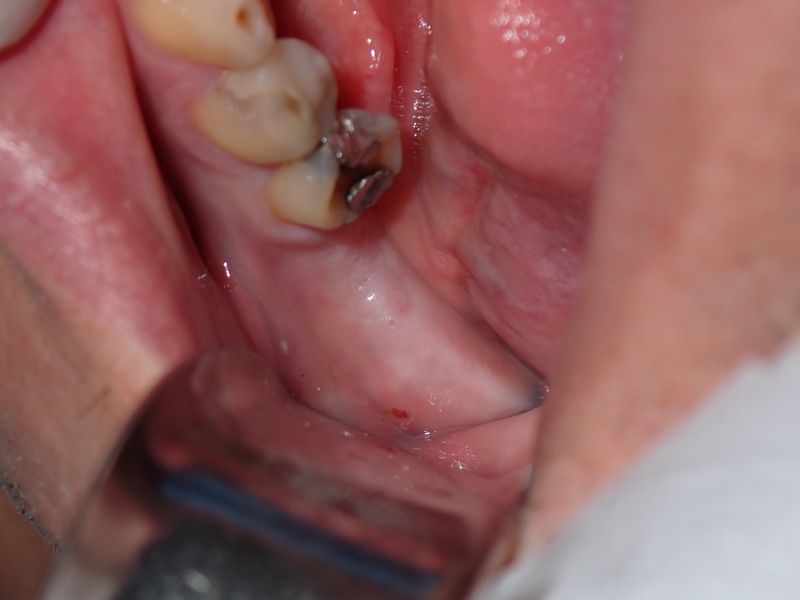

fredlibc | profile | all galleries >> Galleries >> WYu - 36 implant tree view | thumbnails | slideshow

PA180020.JPG (1 of 6)